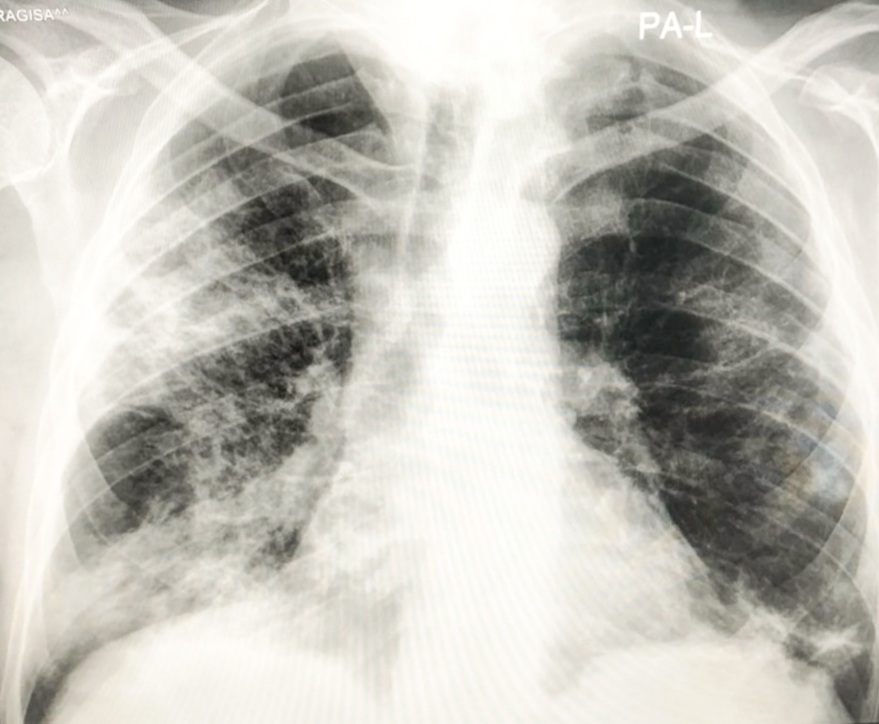

ugrožena', ali je pojasnila i kako dolazi do izuzetno teških slučajeva u kojima se 'čak i za nekoliko sati razviju ekstremno teške pneumonije'.Zabrinjavajuće su slike koje vidimo u medijima – rtg snimke oboljelih osoba koje ljekari opisuju sa ”pacijent gotovo i nema pluća”⬇️.

Vakcinisani mnogo rijeđe obolijevaju od covida-19. Covid može da prođe kao jako blag, ali često znaju da se jave i ekstremno teški oblici, gdje se čak i za nekoliko sati naprave užasne pneumonije koje bukvalno razaraju pluća. Koronavirus ima osobinu da oštećuje endotel krvnih⬇️

i dovodi do trombotičkih poremećaja na plućima i srcu, u mozgu. To je veoma kompleksan mehanitzam poremećaja koji uvodi pacijenta u kritična stanja opasna po život. Ako bolest traje duže od mesec dana, onda govorimo o